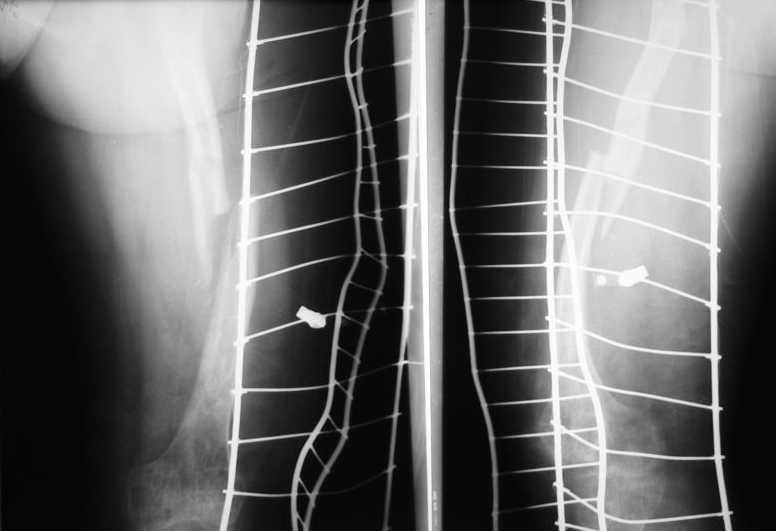

Закрыто заштифтовать не так просто - нужен серьезный опыт: помимо искривления оси бедра у таких больных обычно сужен косттномозговой канал, а сама кость в сечении саблевидная. Хотя механически это оптимально, но провести гвоздь достаточного диаметра для блокирования непросто. У нас была похожая пациентка весной - закончили пластиной. Снимки сейчас продемонстрировать не могу, но интересная фотография участка резецированной кости осталась - в приложении.